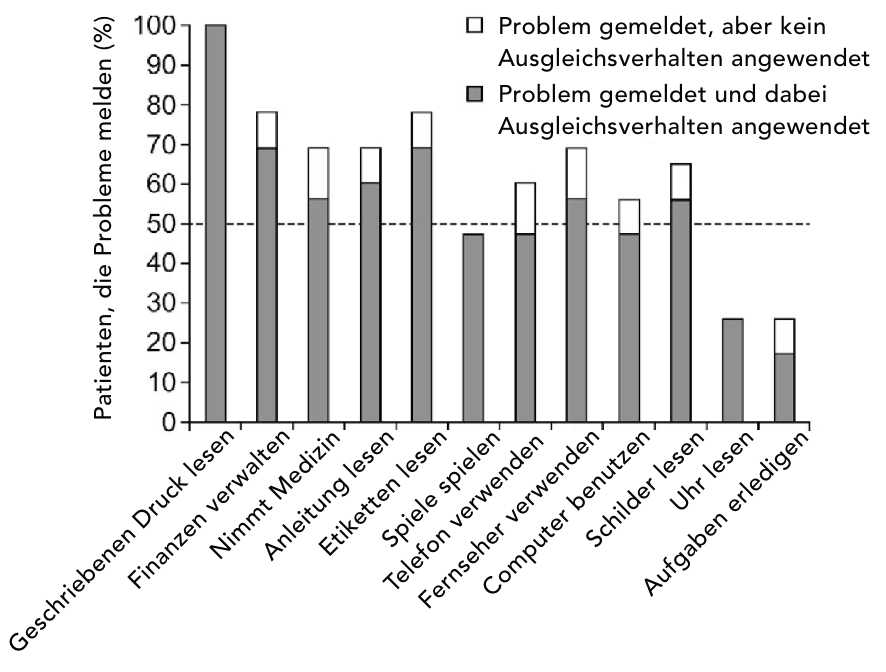

Der Functional Reading Independence Index (FRI-Index)

Der sog. Functional Reading Independence Index (FRI-Index) basiert auf einem Messindex, wobei die Lesefähigkeit einer Person mit GA im Rahmen verschiedener mit Lesen verbundener Aktivitäten vom Patienten beurteilt wird.20

Zu den Parametern des FRI-Index zählen u. a. das Lesen von Etiketten auf Arzneimittelpackungen oder Lebensmitteln, das Lesen zur Abwicklung von Finanzgeschäften und Durchführen von Überweisungen sowie das Lesen von Texten auf einem Fernseher oder Computer.20 Diese Untersuchung ist besonders wichtig für Menschen mit fortgeschrittener trockener AMD oder GA, die oft visuelle Defizite aufweisen können, die mit einer BCVA-Untersuchung nicht erfasst werden.

Probleme mit funktionellen Lese-Aktivitäten haben